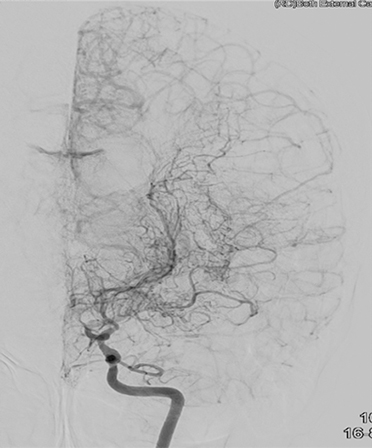

두개내외 뇌혈관우회로수술, 수술 후 뇌혈관조영술 및 뇌관류CT

수술받은 좌측 대뇌반구는 뇌혈류 개선으로 인해 혈류감소를 의미하는 빨간색깔 부위가 사라집니다.